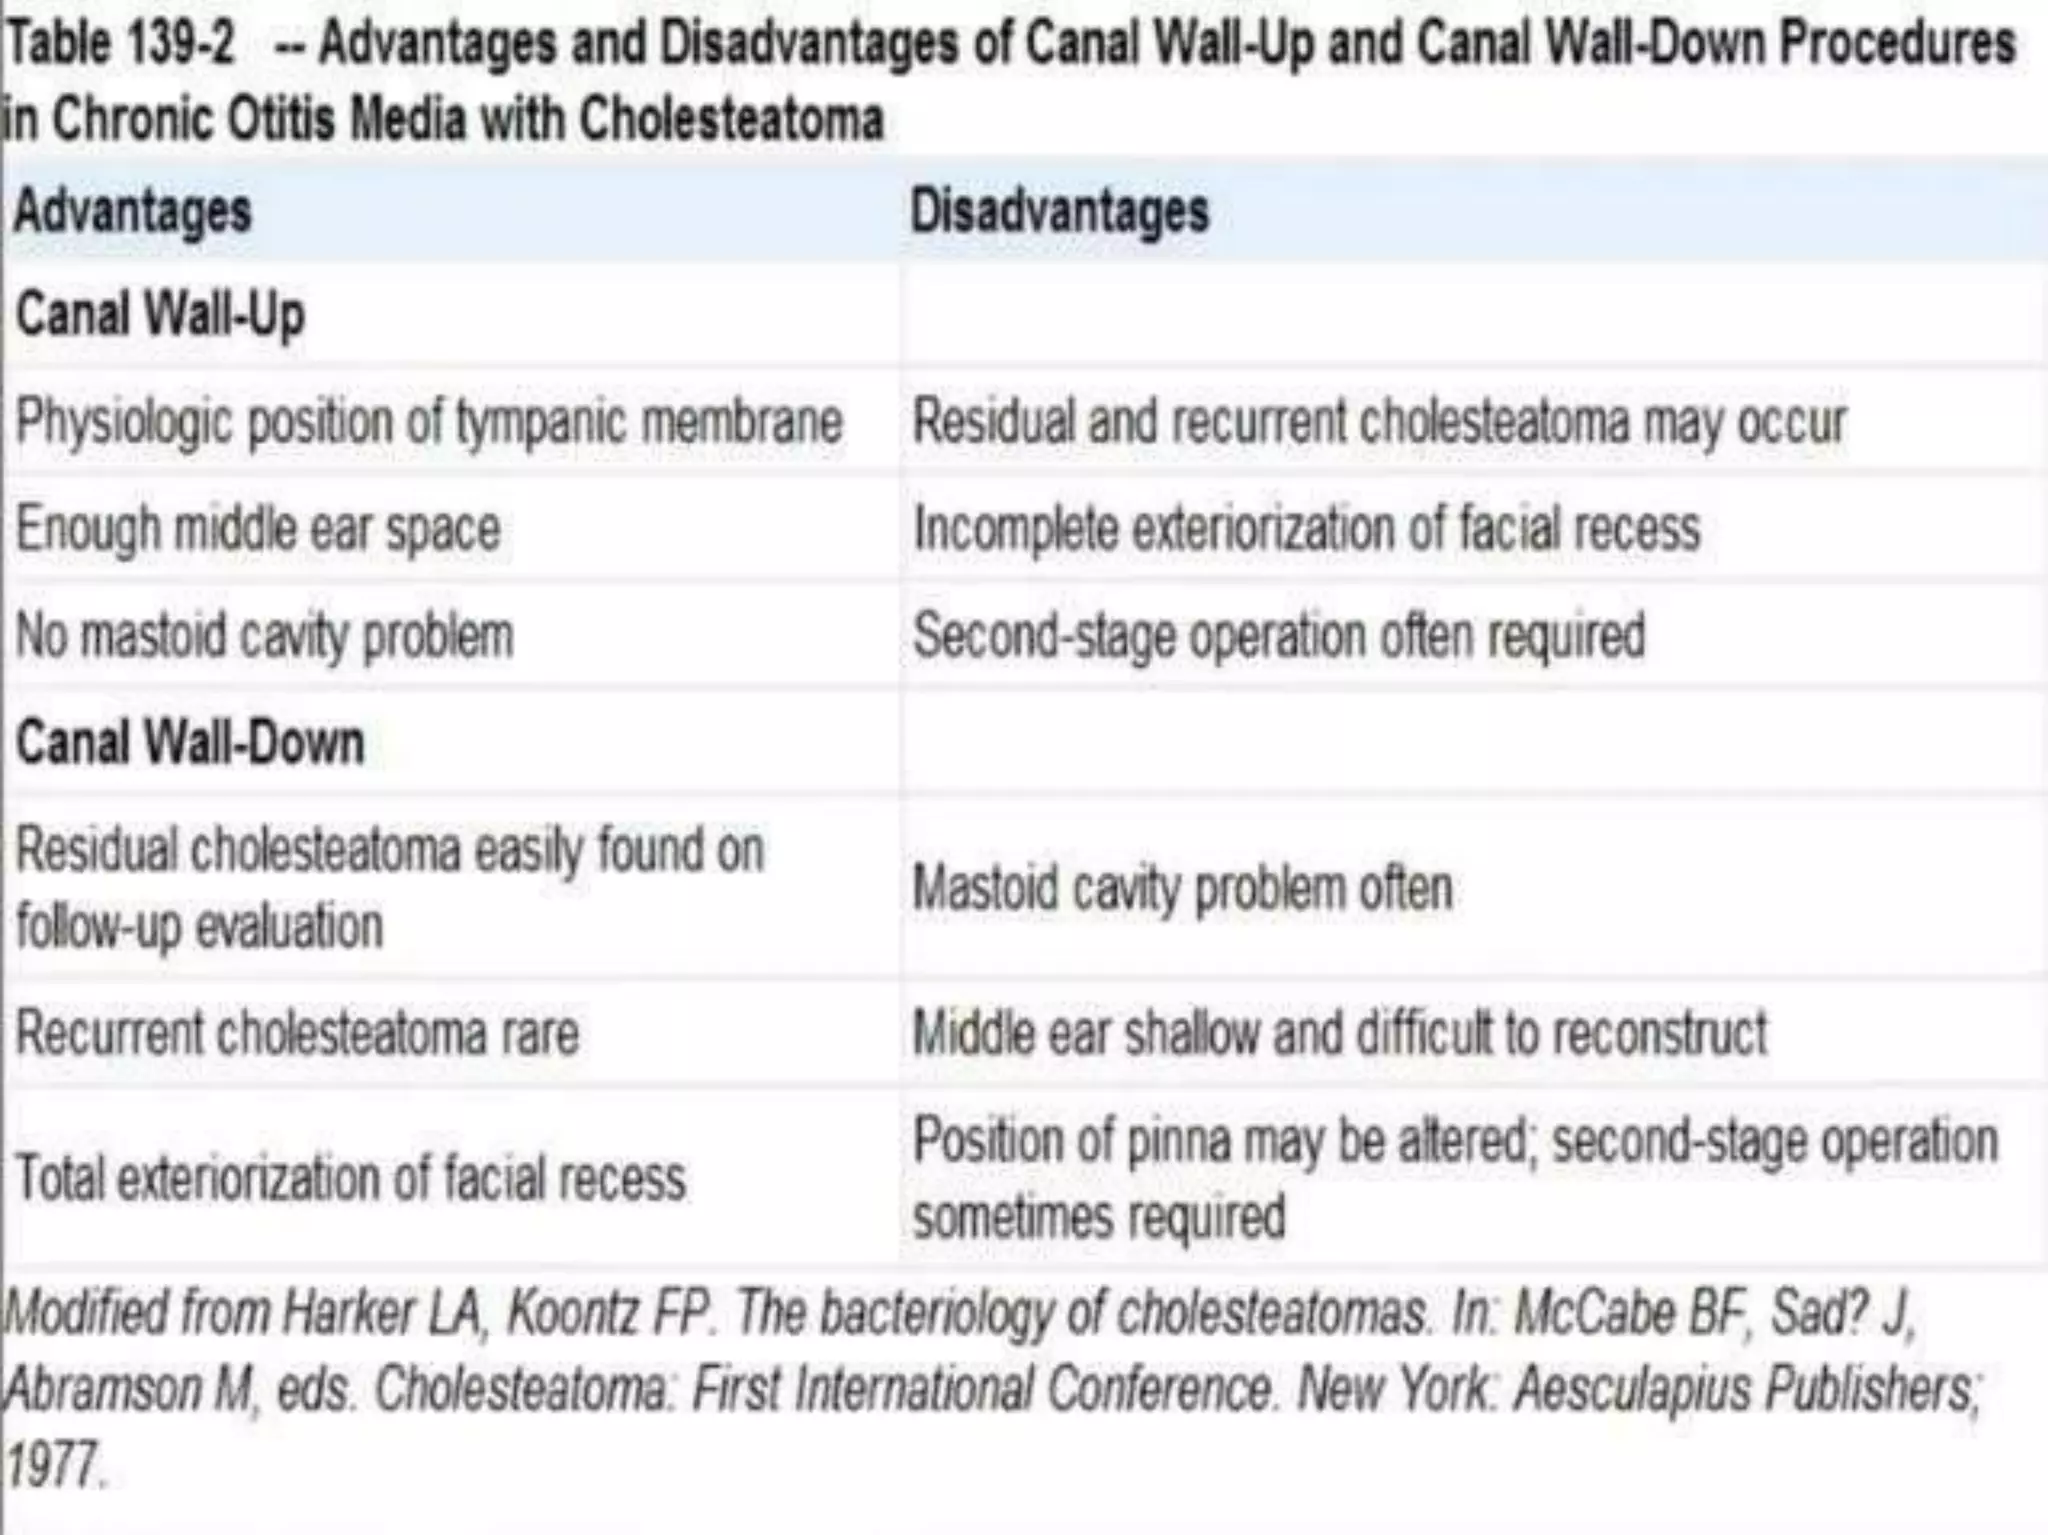

Chronic otitis media is a chronic inflammation of the middle ear and mastoid cavity that presents with recurrent ear discharge through a perforated eardrum. It has several subtypes depending on the state of the eardrum perforation and epithelium. It can be caused by prior acute otitis media, genetics, environment, eustachian tube issues, gastroesophageal reflux disease, craniofacial abnormalities, or immune deficiency.